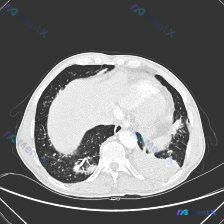

今天拿到一张胸部下肺区CT肺窗横断面片,整理了一下影像和分析思路,跟大家分享一下,这个病例其实挺容易踩坑的。

这是一张放射影像-胸部CT-肺窗-横断面,图像清晰度符合要求,窗宽窗位标准,能清楚观察肺实质,当前层面位于下肺区,能看到心脏轮廓和肝脏上缘,观察范围包括双侧肺下叶、心脏、降主动脉、膈肌顶部和部分肝脏。

影像所见整理

- 背景肺实质:双肺透亮度减低,存在弥漫性密度不均

- 局灶病变细节:

- 右肺下叶:支气管血管束周围增粗,伴随细网格影和小斑片状密度增高影,局部有条索状结构,提示存在间质性改变合并炎性渗出

- 左肺下叶后基底段:可见片状实变影,密度较高、边缘模糊,实变内可见支气管充气征,实变周围伴随网格影和磨玻璃密度影

- 分布特点:病变主要集中在双肺下叶后份和胸膜下区域,同时存在密度增高、网格影和实变三种表现

- 气道和间质:下叶支气管形态尚可,没有明显狭窄或闭塞,但远端分支受病变影响显示不清;可见多发细小网格影和局部小叶间隔增厚,提示肺间质存在炎症或纤维增生

- 胸膜纵隔情况:病变延伸至双侧胸膜下,部分和胸膜关系紧密,但本层面未见明确胸腔积液;心影边缘清晰,左肺下叶病变和心脏纵隔交界区紧密接触